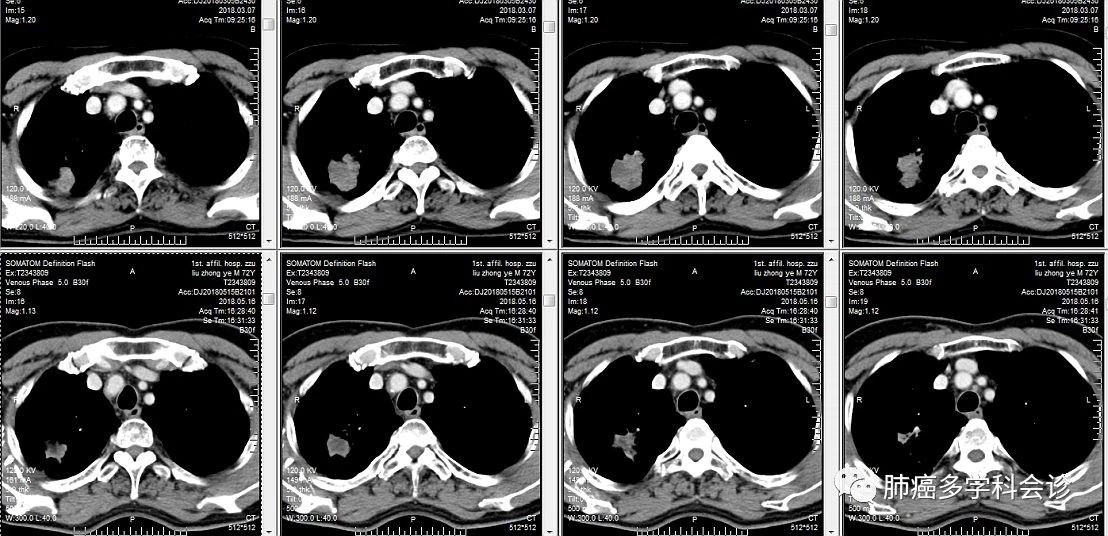

以下为患者在 PD-1抗体治疗前(上一行,2018-3-7)和治疗后(下一行,2018-5-16)胸部 CT 所显示的肿块大小,右上肺的肿块在肺窗(上图)和纵隔窗(下图)都明显退缩。